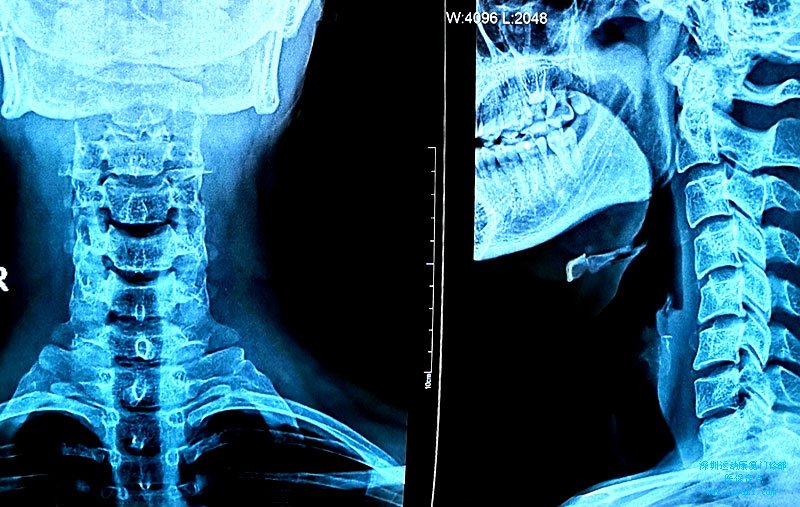

颈椎病治疗二则

病历颈椎病 姓 名:郑xx 性别:男 年龄:32 主诉:颈痛1年。 现病史:患者长期伏案工...

颈肩疼痛颈椎病治疗

姓 名:林 性别:男 年龄:26 主诉:颈肩疼痛2天 现病史:患者2天前因运动不慎扭伤...

颈肩疼痛治疗三则

姓 名:何某 性别:男 年龄:46 主诉:颈肩疼痛1周 现病史:有长期伏案工作史,...

颈部疼痛伴头晕不适2月余-颈椎病(椎动脉型)

颈部疼痛伴头晕不适2月余-颈椎病

姓 名:王某某 性别:女 年龄22岁 主诉:颈部疼痛伴头晕不适2月余。 现病史:患者...

肩颈疼痛2周-颈椎病

姓 名:陈xx 性别:女 年龄:29 主诉:肩颈疼痛2周。 现病史:患者2天前久坐后出现颈...

颈椎病-颈肩疼痛1年

姓 名:陈某 性别:男 年龄:24 首诊时间:9月 主诉:颈肩疼痛1年 现病史:患者有...